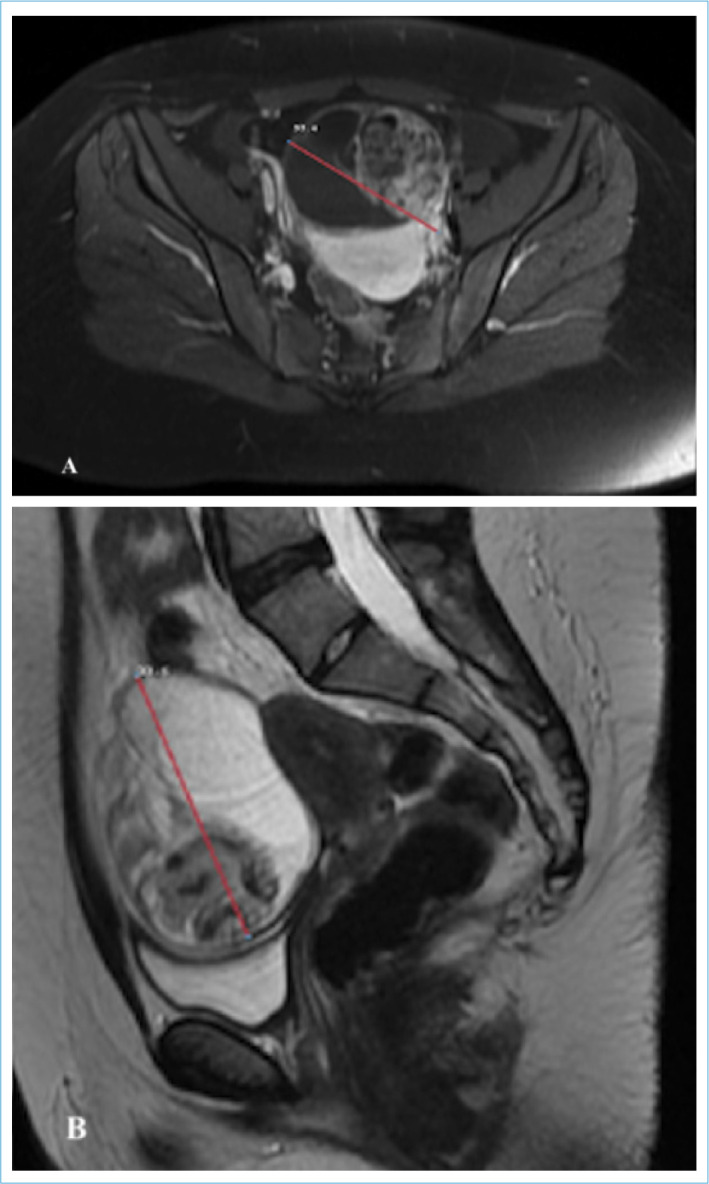

This is a case report of a 19-year-old nulligravid patient with a choroid plexus papilloma tumor in a mature cystic teratoma in the right adnexal area. The patient, who had abdominal pain and dyspepsia, showed a 9 cm diameter mass with a solid/cystic component, initially interpreted as a dermoid cyst in the right adnexal region. Mature cystic teratoma is a benign germ cell tumor and is common in women during the reproductive period. However, choroid plexus papilloma is a rare brain tumor. The diagnosis of ovarian choroid plexus papilloma can be made with imaging tests such as magnetic resonance imaging or computed tomography, and treatment is usually by surgical removal. Only four cases of ovarian teratoma with choroid plexus papilloma have been informed in the English literature, and this issue is the fifth.